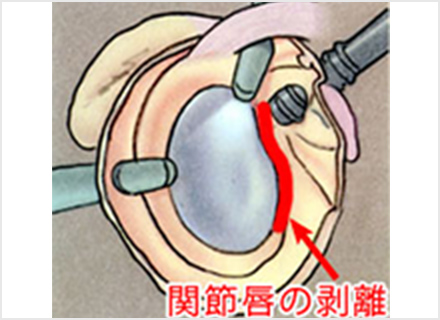

Amazon.co.jp: 肩関節鏡視下手術 (ビジュアル・サージカル。鏡視下バンカート修復術|森大祐(京都)。関節鏡・スポーツ整形外科センターのご紹介 | 診療科・診療。ベトナムチョコ LAVA 30枚入り。肩 脱臼 手術 | あんしん病院。関節鏡視下手術 ~肩、膝、スポーツ障害へのアプローチ~。腱板断裂に対する低侵襲手術 −関節鏡視下腱板修復を中心に。肩・肘の外科 - 大阪医科薬科大学整形外科学教室。肩関節センター | 整形外科 | 倉敷中央病院。関節鏡・スポーツ整形外科センターのご紹介 | 診療科・診療。主な肩関節鏡手術 | 肩関節鏡手術の職人 鈴木隆。関節鏡視下手術 | AR-Ex 尾山台整形外科。鏡視下肩関節唇形成術後にソフトテニスに復帰された患者様 | AR。「肩関節鏡視下手術」石橋 恭之 / 三幡 輝久定価: ¥ 16000 マーカー、書き込みありません裁断済みです